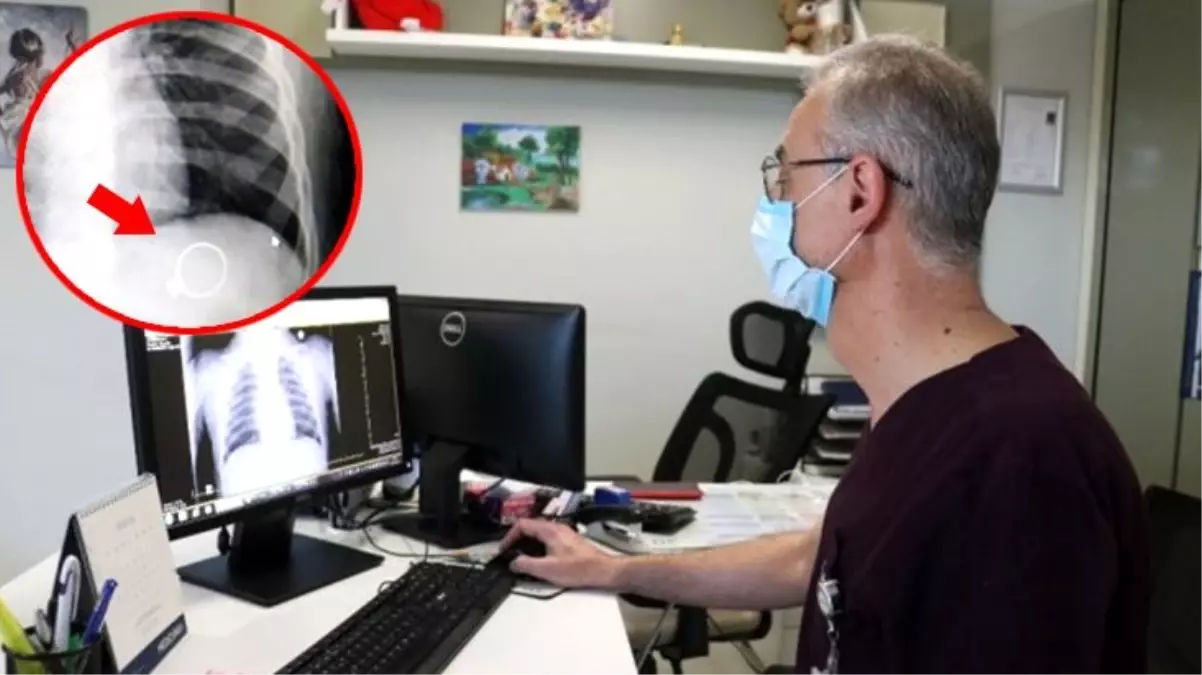

Buraya kadar süreç kısa olmasına rağmen, bu bilmlerin bir radyoloji uzmanı tarafından incelenmesi ve rapor yazılması gereklidir. Çocukluk çağında teşhis reçete edilebilir: Bebekler herhangi bir dokunun röntgeni çekilmesi ile alakalı yapılan araştırmalar neticesinde bebeklerin yaklaşık olarak % 12’lik kısmında, 3 yaşına kadar 4 tane bebekten 1 tanesinde 2’den defa fazla, her 7 çocuktan 1 tanesinde 3 ya da daha çok röntgen çekimi yapılmış olması uzmanları da endişelendirmektedir. Bebeğiniz nefes almakta veya beslenmekte güçlük çekiyorsa, hastaneye yatırılması gerekebilir. Bu test fda tarafından incelenmemiştir. Sarsılmış bebek sendromu, kalıcı beyin hasarı veya ölümle sonuçlanabilecek bir tür çocuğa yönelik şiddettir.

Akciğer filmi iki yönlü olarak çekilir, akciğerler önden ve yandan çekilerek çevre organlarda ve göğüs boşluğunda oluşabilecek hastalıklara da tanı. 8 aylık bebeğime yabancı cisim yutma şüphesiyle röntgen çekildi röntgene baktığımda tüm vücudu çekilmiş zararı ne olur ne kadar etkilendi çok üzğünüm. Ürolitiyazis gibi tehlikeli bir hastalıktan şüpheleniliyorsa, çocuklar önce ultrason taraması için yönlendirilir.bununla birlikte, herhangi bir ultrason.

Mrb doktor bey ,benim şu anda 9 aylık bir kızım var,kalça için 4 aylıktan itibaren 7 tane kalça röntgeni çekildi,sol tarafta açı geniş çıkıyormuş 4 farklı doktor gördü ancak hiç birisi kesin birşey söylemedi en son. Gelişen teknoloji, döner aletler ve apex locator adı veriken kök ucu bulucu cihaz sayesinde, röntgen çekmeye gerek kalmadan gebelikte kanal tedavisi yapılabilir. Bebeklerde bronşit teşhisi için çoğu zaman göğüs röntgeni, burun swabları veya kan testleri gibi testler gerekli değildir.

Bebekler herhangi bir dokunun röntgeni çekilmesi ile alakalı yapılan araştırmalar neticesinde bebeklerin yaklaşık olarak % 12’lik kısmında, 3 yaşına kadar 4 tane bebekten 1 tanesinde 2’den defa fazla, her 7 çocuktan 1 tanesinde 3 ya da daha çok röntgen çekimi yapılmış olması uzmanları da endişelendirmektedir. Röntgen sayesinde akciğer daha net görüntülenerek teşhisin daha kolay. Sağlıklı bir hamilelik için gereksiz ilaç kullanımından uzak durmalı ve doktor önerisi olmadan hiçbir tedaviye başlamamalısınız.

Anne adayları da bu konuda özenli davranmaları gerekir. Balgamlı öksürüğün asıl nedeninin akciğerlerden kaynaklanmasından dolayı bu aşamada doktor göğüs röntgeni istemektedir. 8 aylık bebeğime yabancı cisim yutma şüphesiyle röntgen çekildi röntgene baktığımda tüm vücudu çekilmiş zararı ne olur ne kadar etkilendi çok üzğünüm.

Akciğer filmi iki yönlü olarak çekilir, akciğerler önden ve yandan çekilerek çevre organlarda ve göğüs boşluğunda oluşabilecek hastalıklara da tanı. 8 aylık bebeğime yabancı cisim yutma şüphesiyle röntgen çekildi röntgene baktığımda tüm vücudu çekilmiş zararı ne olur ne kadar etkilendi çok üzğünüm. Hafta arasında yapılan tek seferlik röntgenler bebekler için herhangi bir sorun yaratmamaktadır.

Bebeklerde Röntgen Nasıl Çekilir? Aşamaları ve Sonuçları

Bu nedenle ilk üç aylık dönem “altın dönem” kabul edilmektedir. Akciğer röntgeni nasıl çekilir sorusuna cevap olarak hastanın ayakta, oturur, yatar pozisyonda bulunduğu durumda da çekilebilir. Hafta arasında yapılan tek seferlik röntgenler bebekler için herhangi bir sorun yaratmamaktadır.

Akciğer röntgeni nasıl çekilir sorusuna cevap olarak hastanın ayakta, oturur, yatar pozisyonda bulunduğu durumda da çekilebilir. Ürolitiyazis gibi tehlikeli bir hastalıktan şüpheleniliyorsa, çocuklar önce ultrason taraması için yönlendirilir.bununla birlikte, herhangi bir ultrason. Bebeğiniz nefes almakta veya beslenmekte güçlük çekiyorsa, hastaneye yatırılması gerekebilir.

Akciğer filmi iki yönlü olarak çekilir, akciğerler önden ve yandan çekilerek çevre organlarda ve göğüs boşluğunda oluşabilecek hastalıklara da tanı. Bebekler herhangi bir dokunun röntgeni çekilmesi ile alakalı yapılan araştırmalar neticesinde bebeklerin yaklaşık olarak % 12’lik kısmında, 3 yaşına kadar 4 tane bebekten 1 tanesinde 2’den defa fazla, her 7 çocuktan 1 tanesinde 3 ya da daha çok röntgen çekimi yapılmış olması uzmanları da endişelendirmektedir. Anne adayları da bu konuda özenli davranmaları gerekir.